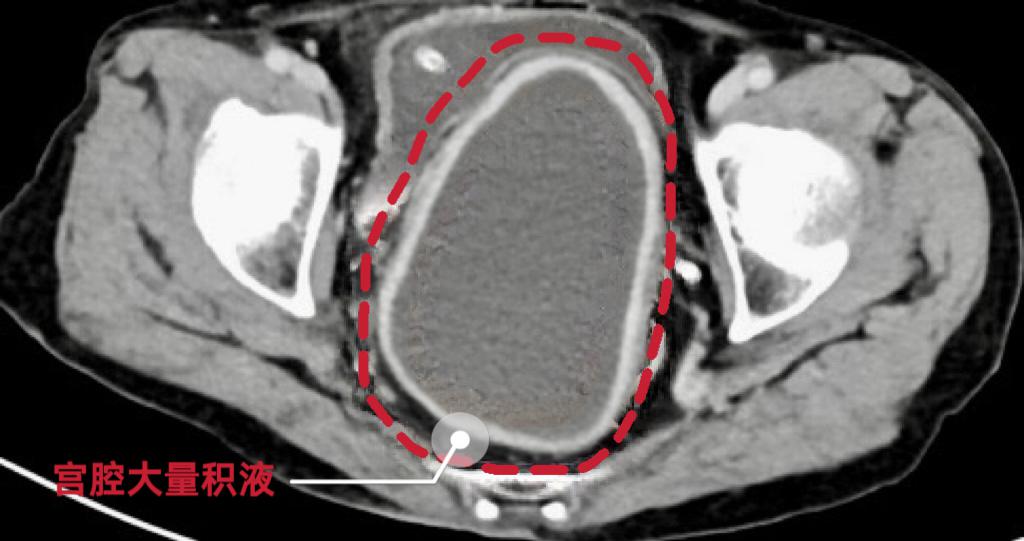

该院妇产科一区黄佼主任介绍,经过询问家属病史了解到,老人一个月前出现过腹痛情况,后面伴随有精神食欲差、嗜睡、逐渐消瘦等症状。此次入院时老人神志模糊,血压下降,血糖波动剧烈,最低血糖仅1.7mmol/L,生命体征极不稳定,腹部CT显示盆腔内巨大包块,考虑“宫腔积脓、感染性休克、严重低血糖”立即收治入院。

在血糖控制稳定后,黄佼主任团队为患者实施了彩超引导下的阴道内镜下宫颈管粘连分离及脓液引流术,术中发现患者阴道萎缩环状缩窄明显、宫颈管严重粘连,内镜下分离粘连后发现宫腔内积聚大量黄绿色、带有腥臭味的脓液。经过精心操作,成功引流出脓液约250ml。术后患者神志逐渐清醒,血压回升,血糖稳定,感染指标明显下降。